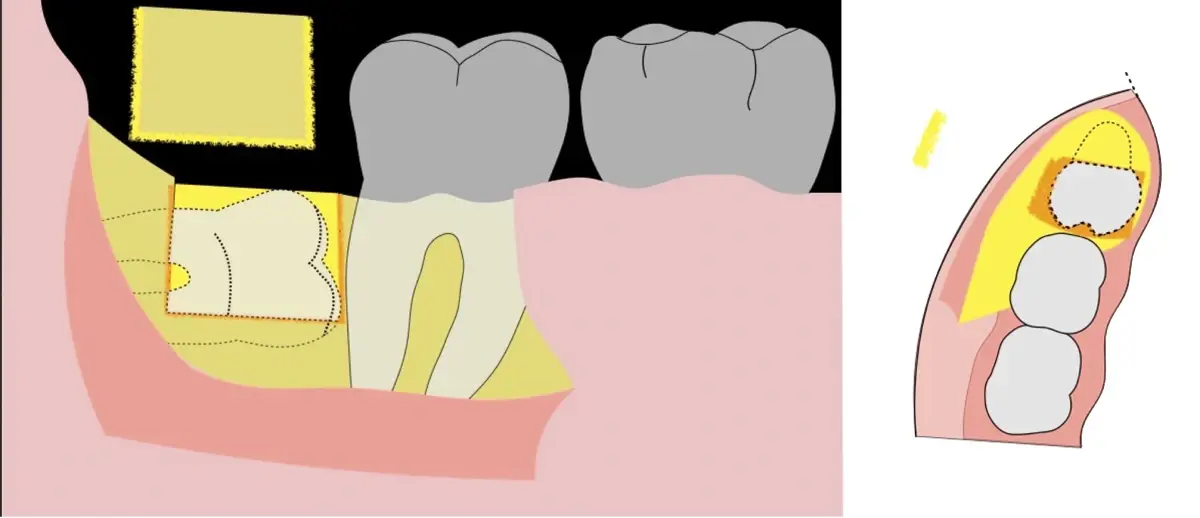

El instrumento piezoeléctrico utiliza un corte micrométrico que retira un área de superficie mínima de hueso, y reduce el riesgo de termonecrosis marginal en comparación con las fresas rotatorias convencionales.

En contraste, el instrumento piezoeléctrico utiliza un corte micrométrico que retira un área de superficie mínima de hueso, y reduce el riesgo de termonecrosis marginal en comparación con las fresas rotatorias convencionales.9 Los micromovimientos mejoran la precisión en el corte y el control táctil, y eliminan las macrovibraciones que se producen con los instrumentos rotatorios.10 Su frecuencia de oscilación es la amplitud de 60-200 μm horizontalmente y de 20-60 μm en sentido vertical, lo que es muy inferior en comparación con las micro sierras oscilantes; por lo tanto, proporciona cortes de osteotomía precisos y seguros. Adicionalmente, posee vibraciones ultrasónicas que descomponen el líquido de irrigación en partículas muy pequeñas (fenómeno de cavitación, que produce un efecto hemostático y así reduce la pérdida de sangre), lo que proporciona una visión clara y sin obstáculos del campo quirúrgico11,12.